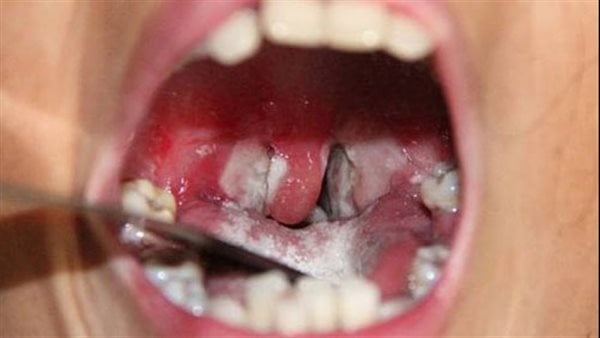

الأخبار (نواكشوط) – قال وزارة الصحة إن مجموع حالات المشتبه بإصابتها بوباء الدفتيريا “الخناق” في ولاية العصابة، بلغ 90 حالة، توفيت منها 8، وشفيت 62 حالة، وما زالت 20 حالة تحت العلاج.

وأكدت الوزارة أن 84 حالة مشتبه فيها، تم تسجيلها في كنكوصة، بولاية العصابة، منها 62 حالة شُفيت بالكامل، و15 حالة ما تزال تحت العلاج، بينما بلغ عدد الوفيات 7 حالات، منها 4 حالات وفاة منزلية لم تخضع لاستشارة طبية سابقة.

كما أكدت الوزارة تسجيل 6 حالات في مقاطعة كرو، توفيت واحدة منها، و5 تحت العلاج.

وفي هذا العام 2025 تم تسجيل 202 حالة إصابة من هذا المرض بولايات الحوضين والعصابه، شُفيت منها 154 حالة، وتوفيت 15 حالة (7 في العصابه + 8 في الحوض الغربي)، هذا في حين تخضع 41 حالة للعلاج، منها 22 في المستشفيات و19 في العلاج الخارجي.